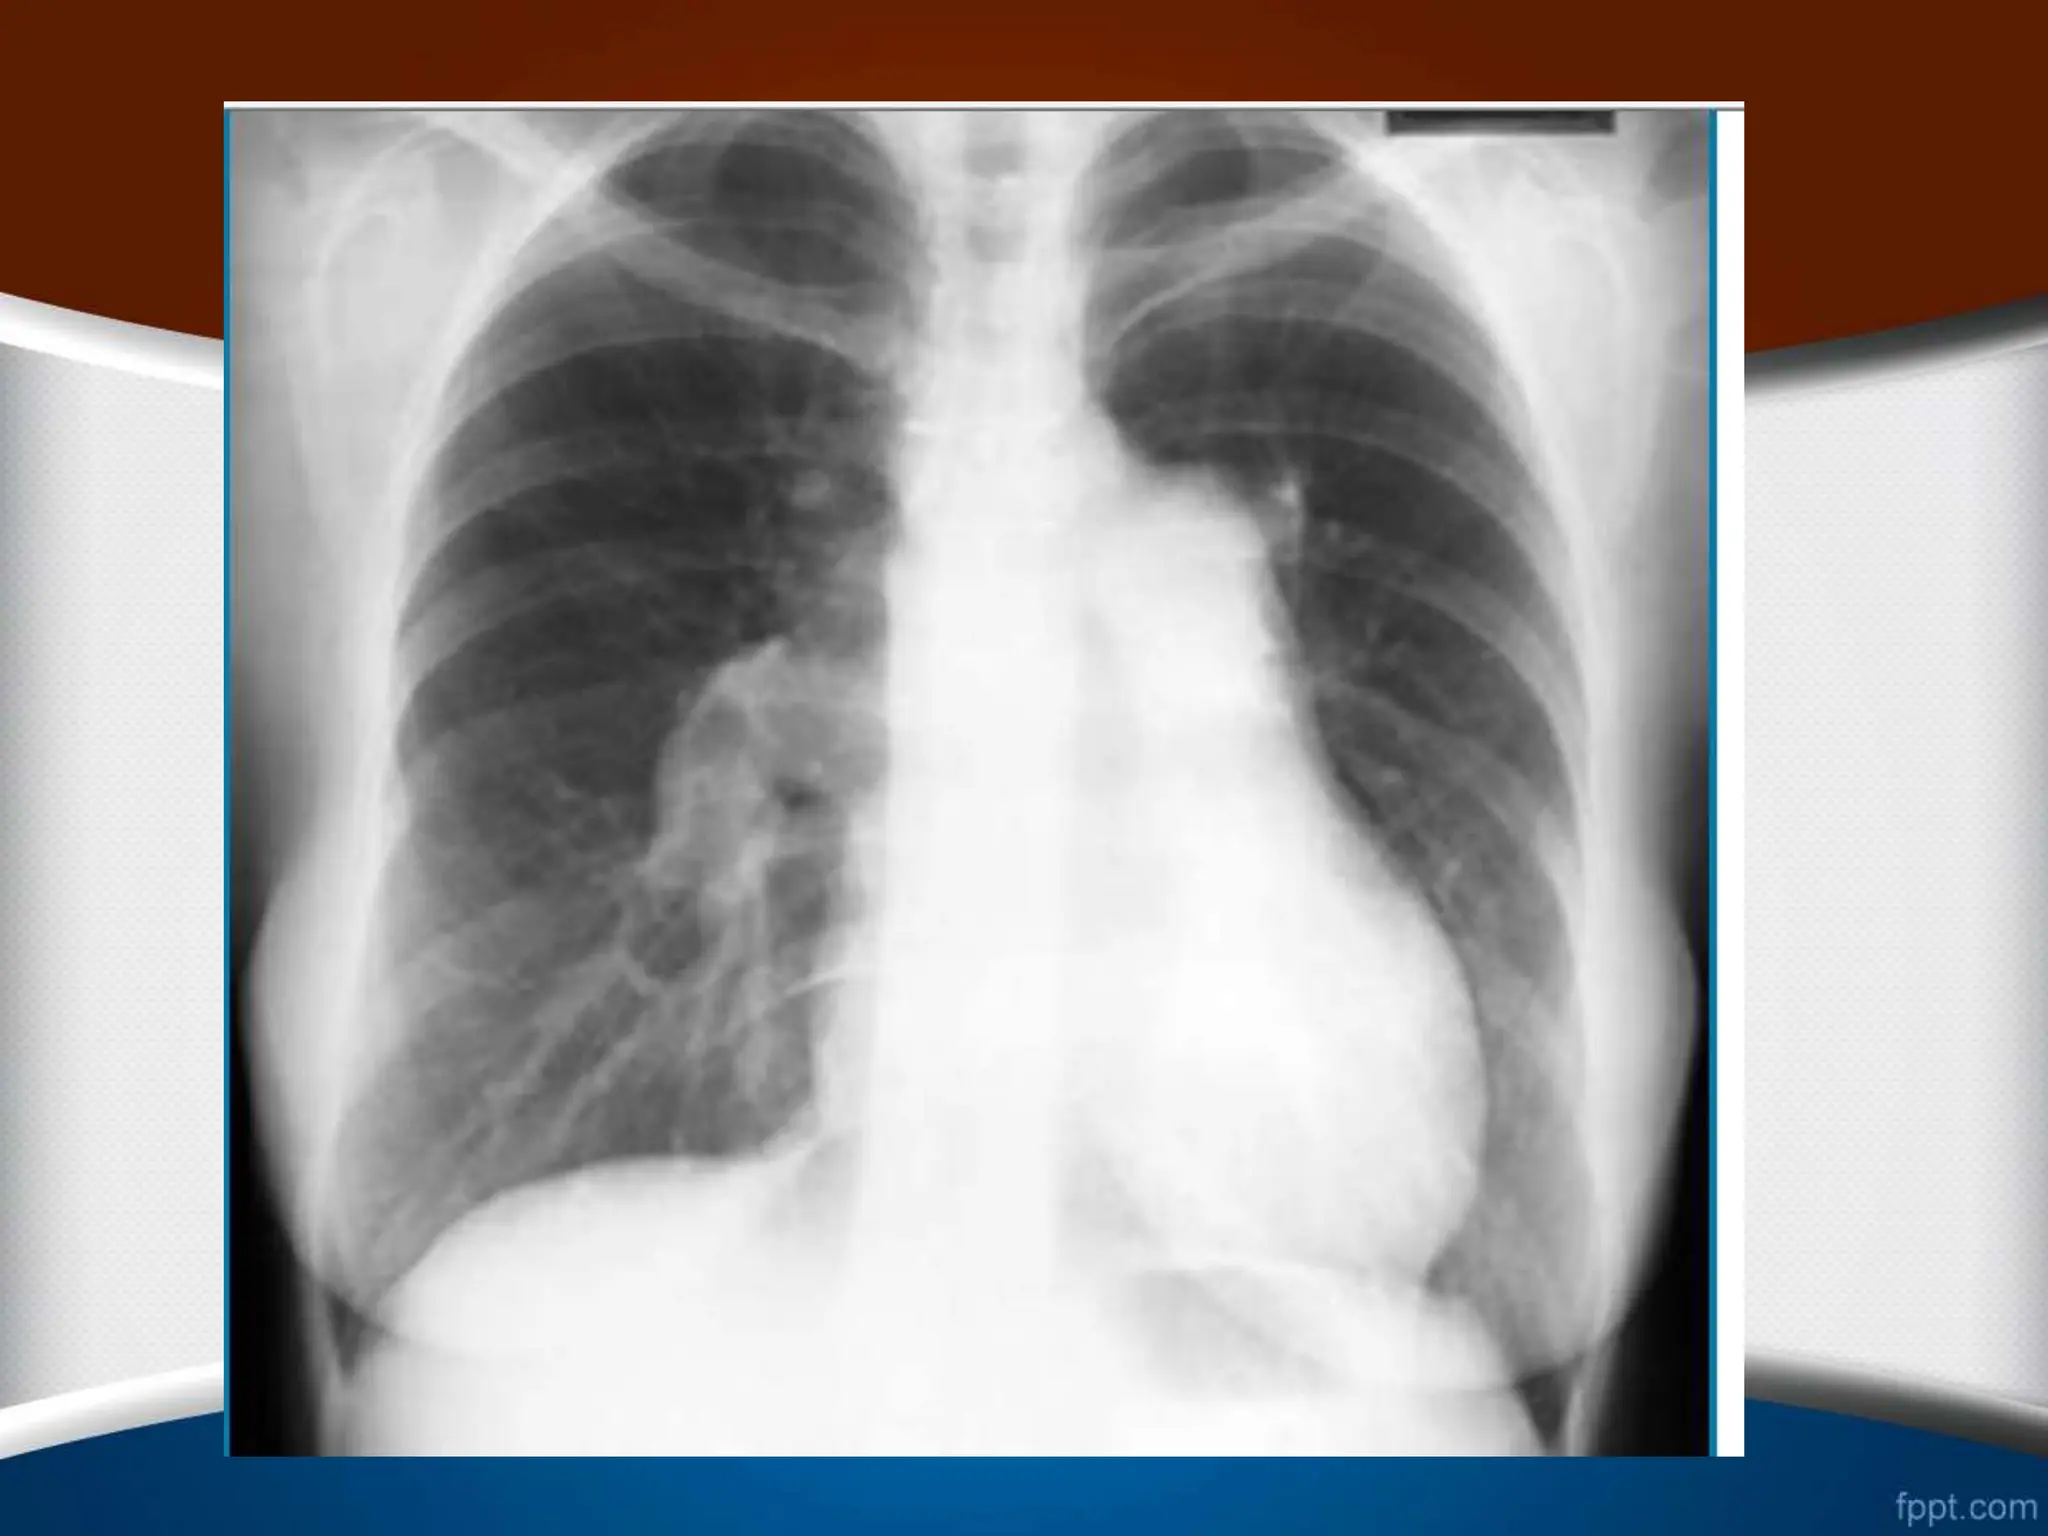

‫بطن‬ ‫یا‬ ‫و‬ ‫چپ‬ ‫بطن‬ ‫بزرگی‬ ‫از‬ ‫ناشی‬ ‫کاردیومگالی‬ ‫علت‬ ‫افتراق‬

‫راست‬

•

‫کننده‬ ‫کمک‬ ‫قلبی‬ ‫بیماری‬ ‫سابقه‬ ‫و‬ ‫حال‬ ‫شرح‬ ‫به‬ ‫توجه‬

‫است‬

.

‫پولمونر‬ ‫تنه‬ ‫اتساع‬ ‫و‬ ‫ریوی‬ ‫قلبی‬ ‫بیماری‬ ‫مثال‬ ‫برای‬

‫به‬ ‫شک‬

‫آئو‬ ‫اتساع‬ ‫طرفی‬ ‫از‬ ‫و‬ ‫افزاید‬ ‫می‬ ‫را‬ ‫راست‬ ‫بطن‬ ‫بزرگی‬

‫رت‬

‫م‬ ‫افزایش‬ ‫را‬ ‫چپ‬ ‫بطن‬ ‫بزرگی‬ ‫وجود‬ ‫احتمال‬ ‫نیز‬ ‫صعودی‬

‫ی‬

‫دهد‬

‫است‬ ‫کننده‬ ‫کمک‬ ‫نیز‬ ‫لترال‬ ‫رادیوگرافی‬ ‫از‬ ‫استفاده‬

‫در‬

‫بزرگی‬ ‫موارد‬

LV

‫در‬ ‫و‬ ‫رتروکاردیاک‬ ‫فضای‬ ‫شدن‬ ‫پر‬ ،

RV

‫بی‬ ‫به‬ ‫رترواسترنال‬ ‫فضای‬ ‫شدن‬ ‫پر‬ ،

‫ش‬

‫از‬

30

%

‫تا‬

50

‫شود‬ ‫می‬ ‫دیده‬